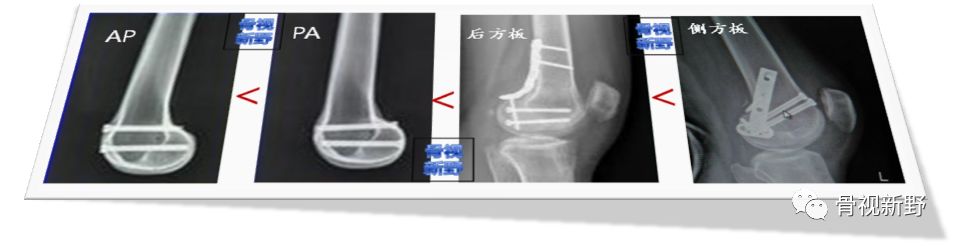

Hoffa骨折最经典的固定方式是拉力螺钉由前向后(AP)固定,因为入路、显露及固定容易;同时,可从髁上非关节面入钉,避免了关节软骨损伤。

但研究发现,从后向前(PA)植入拉力螺钉对骨折固定的强度和稳定性显著高于由前向后(AP)置入的螺钉[Soni A 2012;Jarit GT 2006]。

选择PA还是AP置钉,还需考虑如下几个问题:

• 手术入路:PA得从后方(后外或后内)入路,暴露及置钉操作较困难,血管、神经损伤的风险高;破坏残存血运,有可能增加骨块的缺血坏死。

• 分型固定:如Letenneur I、III型骨折块较大,AP固定后方有较大的抓持骨块;但II型,尤其IIb/IIc型,后方骨折块较小,PA固定后螺钉前方抓持骨块大,强度自然比AP固定要高。

• 软骨保护:PA置顶,螺钉必然要穿过软骨面,大直径螺钉必须得埋头处理,势必造成较大的软骨缺损。